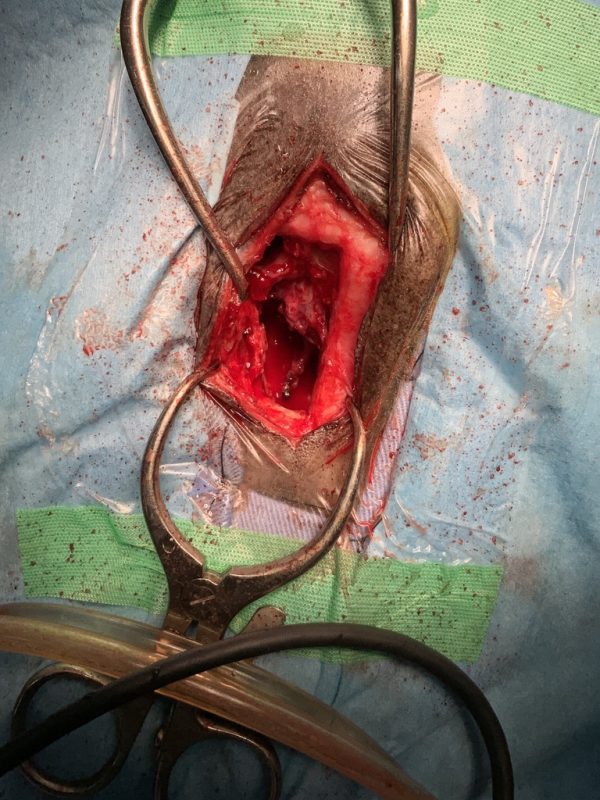

膿が出た

【2026年1月21日(水)】

宇宙くん鼻の上の手術跡が開いてしまって膿が出てるかも。

そらうみママに病院連れて行ってもらいます。

昨日の写真のこの部分の皮膚が破れたみたいですね。

病院に連れて行った

宇宙を病院に連れていってきました。 やはり鼻の上の手術跡の下の部分に穴があいており、化膿して膿が出ていました。

放射線治療の影響で皮膚が薄くなっている上、手術で骨も削っているため、そこに穴があいてしまったようです。

昨日、宇宙の右目が腫れていたのも、この碧海・・いや、膿が原因だと思います。

いまも傷から膿が出続けていますが、穴を縫うことはできないそうで、皮膚が再生し、傷口が自然に治るのを待つしかないとのことです。

放射線治療をしているため傷口が治りにくくなっており、抗生剤を飲みながら回復を待つことになります。